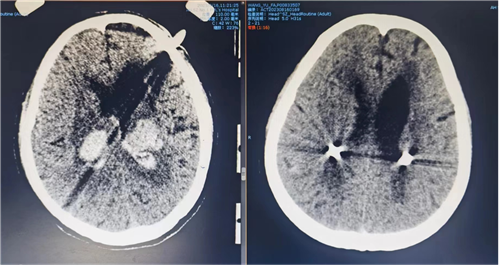

家住山东省滨州市的刘先生,在宿州市工作的时候,突然意识丧失、昏迷不醒,朋友立马拨打了120急救电话将其送到我院。紧急入院后,急诊科医生检查发现患者头颅CT提示脑干大量出血,出血量已超过10毫升,患者呈重度昏迷状态,病情危重,自主呼吸节律极为紊乱,急诊予紧急插管上呼吸机,为进一步抢救治疗,收住神经外科重症病区。

术前,脑血管病诊疗中心团队为患者安装头架后行头CT扫描,选取穿刺靶点,计算X、Y、Z轴值。选取合适手术体位,消毒铺单后安装弓架导向系统,调整X、Y、Z轴值与计算值一致后,用带针芯引流管在定向仪引导下穿入血肿腔,注射器抽吸暗红色血液及血凝块8ml,留置引流管。